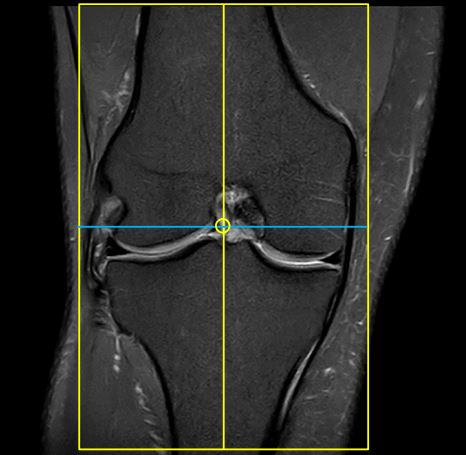

Wie sind die verschiedenen Graustufen auf dem MRT-Bild zu deuten?

MRT-Bilder zeigen verschiedene Gewebearten in unterschiedlichen Graustufen. Helles Gewebe bedeutet in der Regel einen hohen Wassergehalt (z. B. Gelenkflüssigkeit oder Entzündungen), während dunklere Bereiche eher feste Strukturen wie Knochen oder Bänder darstellen. Der genaue Kontrast hängt jedoch von der verwendeten Sequenz ab. Eine sichere Beurteilung kann nur durch eine ärztliche Analyse erfolgen.

Die folgenden Bilder zeigen MRT-Aufnahmen eines Knies aus verschiedenen Perspektiven: